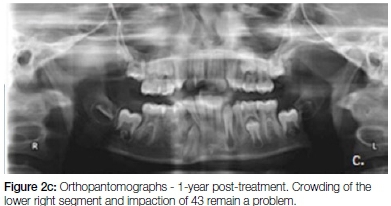

The patient was recalled daily for seven days postopera-tively for irrigation of the socket with betadine and saline. The parents of the patient were taught how to irrigate the socket with these solutions and how to ensure the maintenance of good oral hygiene. Thereafter the patient was recalled fortnightly and periodic trimming of the acrylic extension was done to facilitate eruption of 44 and 45. After three months (Figure 5, a-c), anterior crossbite correction was observed along-with progressive eruption of 44 and 45. The 43 appeared to be improving in its path of eruption. The patient was then advised to discontinue the obturator. Follow-up after one year showed complete eruption of 44 and 45, and no relapse of the crossbites or recurrence of the dentigerous cyst (Figure 2c and Figure 6, a-c).

In this case, posterior bite blocks were incorporated in the obturator bilaterally to dis-occlude the anterior teeth and assist in self-correction of cross bite of the lin-gually locked maxillary incisors. The main advantage of this modification is that it obviated the need for a second appliance to correct the cross bite. The appliance was also easily constructed although speech and mastication difficulties were of concern to the patient for the first few days, after which he became accustomed to manipulating the device. The results of the modified obturator were encouraging and the one year follow-up did not show any sign of recurrence of the cyst or relapse of the cross bite. The lower right first molar has drifted mesially and further orthodontic treatment remains a requirement to deal with crowding, overjet, midline discrepancy and impaction of the lower right canine.